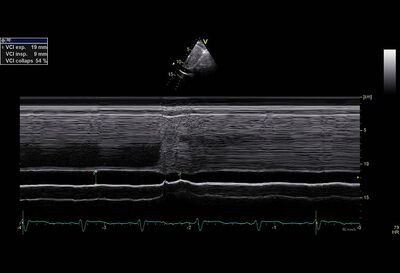

Subcostale view M-mode collapse VCI

Inferior vena cava diameter

normal borderline dilated

<15mm 15 - 20mm >20mm

Respiratory failure

In a normal RA pressure collapses the VCI in 80% of the cases, >40% (measured at the mouth of the hepatic vein). ±40% collapse VCI corresponds to a pressure of 8-10mmHg. At a collapse of 60-70%, the pressure in the VCI most often 2-4mmHg. At a collapse <40%, the VCI pressure >10mmHg (85%). When dilated, not collapsing VCI can pressure 20-25mmHg.